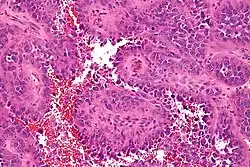

![]() Naczyniakomięsak – obraz mikroskopowy | |

Naczyniakomięsak (łac. angiosarcoma) – nowotwór złośliwy wywodzący się z komórek tworzących śródbłonek naczyń krwionośnych, należy do grupy mięsaków tkanek miękkich. Ma bardzo wysoką tendencję do tworzenia przerzutów m.in. do wątroby i mózgu. Może powstać po narażeniu na działanie chlorku winylu i związków arsenu.